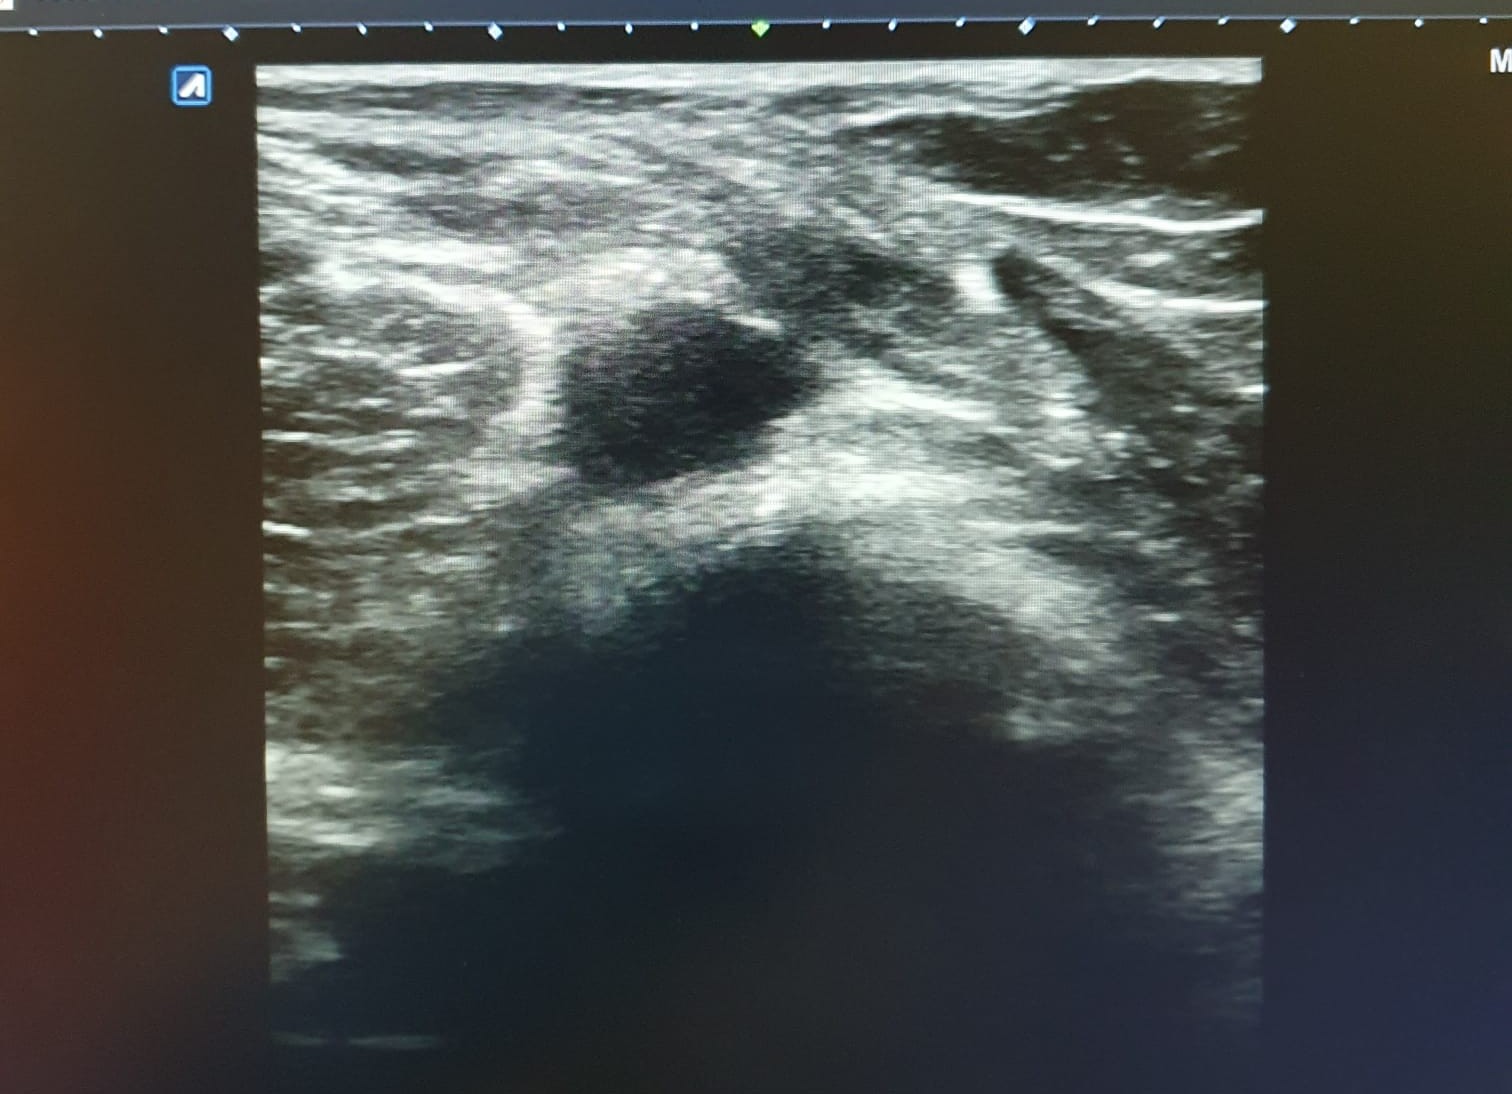

Hallazgos ecográficos

Ecografía de rodilla. Compartimento lateral: imagen anecoica/hipoecoica 10 x 5 mm en zona proximal de ligamento colateral lateral, sugestivo de rotura parcial. Compartimento posterior: imagen anecoica 20 x 30 mm sugestivo de quiste de Baker. No otras alteraciones ecográficas.